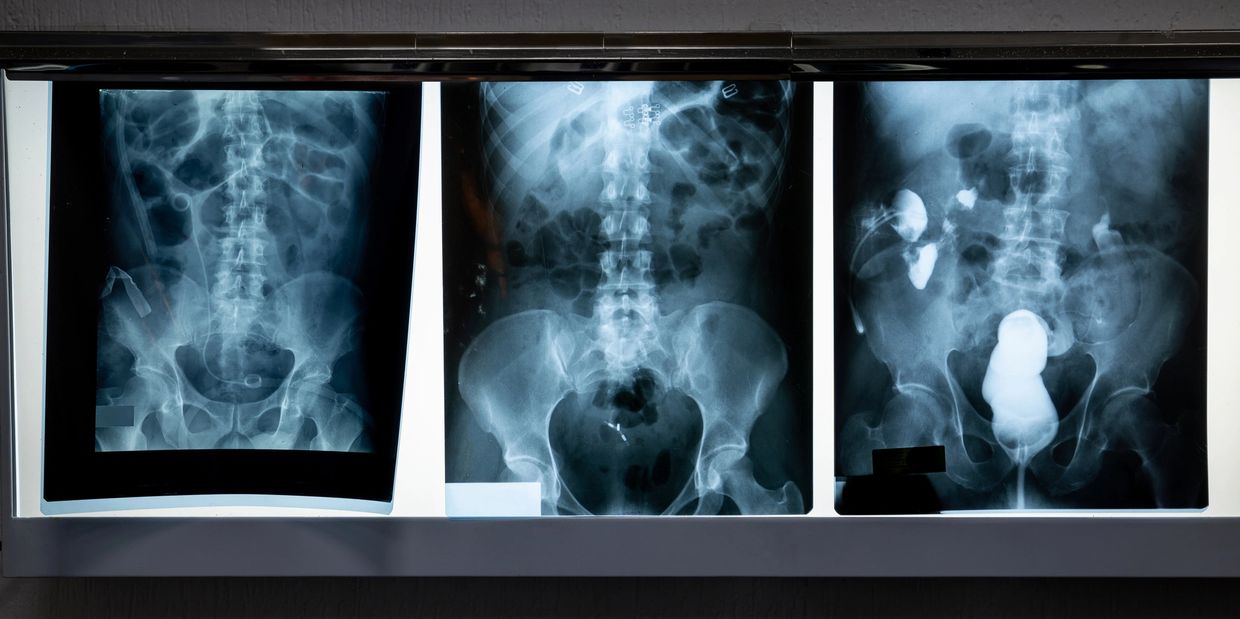

General X-rays are one of the most common and valuable diagnostic tools used in modern medicine. They provide clear images of the body’s internal structures, including bones, joints, and certain soft tissues, helping doctors quickly identify fractures, infections, abnormalities, and other health conditions.

At MOXS, we use state-of-the-art digital X-ray technology to ensure exceptional image quality, faster results, and reduced radiation exposure for our patients. Whether it’s a routine check, injury assessment, or part of a broader diagnostic process, our professional radiography team ensures a comfortable, safe, and efficient experience from start to finish.